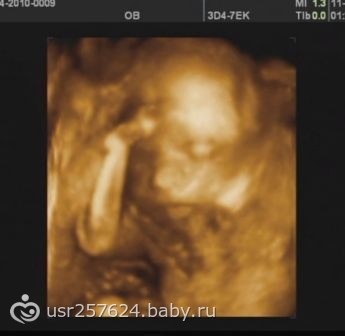

Узи на 12 нед подскажите!!!!!!

Пол малышаМногие говорят что узист уже говорит пол ребенка на 12 нед на узи.Какое именно 3 д или 2 д?Хочется хотя бы предположитеьно,как вы думаете какое подойдет.С первым только на 20 нед сделала 3д и сказали пол(((((